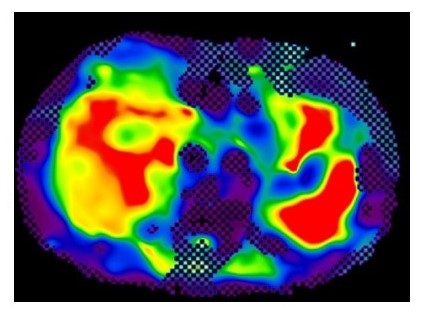

ウイルス肝炎以外の「非ウイルス性肝障害」には比較的女性に多い自己免疫性肝炎や原発性胆汁性胆管炎等の疾患がありますが、中でも最近患者数が増えて大きな問題になってきているのが脂肪性肝疾患(NAFLD)です。さらに肝硬変に進んでいく可能性の高いものをNASHといい、わが国でも肝細胞癌の原因として年々このNASHによるものが増えてきています。かつて「脂肪肝では肝臓の数値は上がるが、肝臓は傷まない」と考えられていた時代もあったようですが、最近の研究により、脂肪肝の方の相当数に肝臓が肝硬変に向けて進み始めている人がいることがわかってきました。ただ、検診などで脂肪肝であることを指摘される人はたくさんいます。その中で自分が肝硬変に向かっていくタイプの脂肪肝ではないか、つまりNASHなのではないかを一度調べておくことをお勧めします。ウイルス性肝炎でもそうですが肝臓が肝硬変に向かって進みだすと肝臓の中に線維が増えてきて肝臓が硬くなっていきます(「肝硬変」という名前の由来です)。現在では腹部のエコーやMRI検査(図2)などによりかなり正確に肝臓の硬さ・肝臓の中の線維の量が測定できます。これで線維化が疑われた場合にはさらに肝生検といって肝臓に針を刺して細胞を取り、病態を確認します。

図2:MRIによる(肝硬度)肝臓の硬さ・肝硬変へ進行の程度の測定